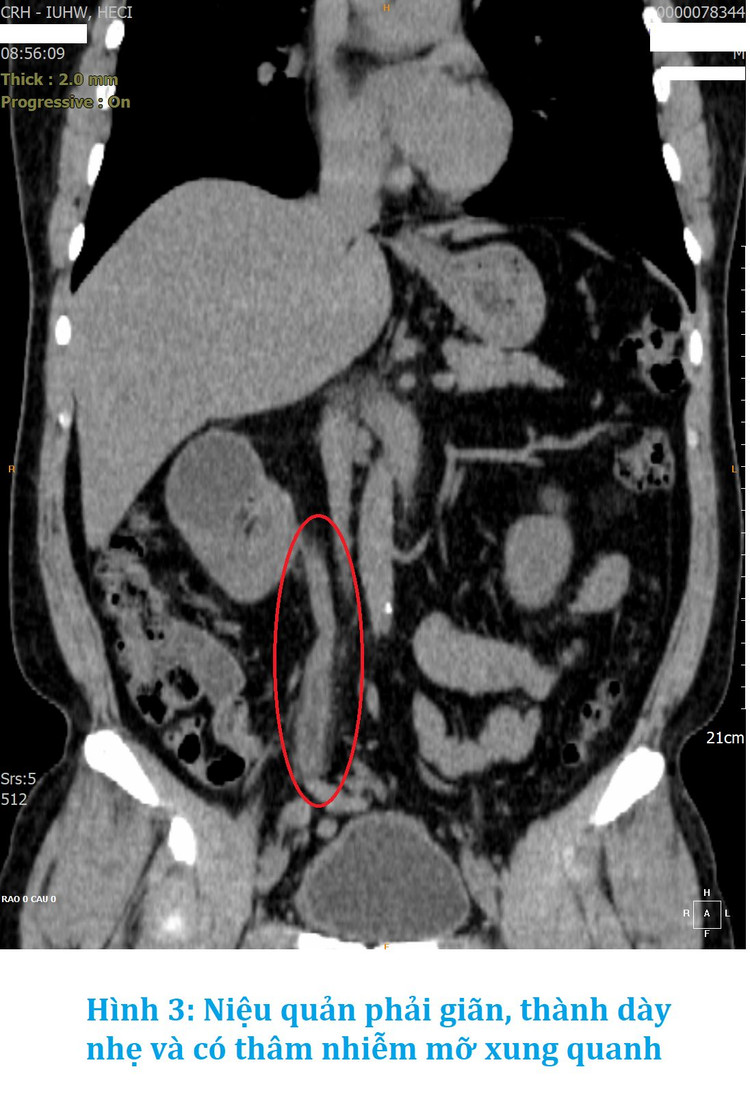

Vừa qua, đi khám sức khỏe tổng quát tại Trung tâm kiểm tra sức khỏe Chợ Rẫy Việt Nhật (HECI), với gói khám Gold, bệnh nhân được chụp CT-Scan toàn thân đã phát hiện thận phải bị ứ nước độ 1, dày đều nhẹ thành bể thận và niệu quản, thâm nhiễm mỡ nhẹ xung quanh, dày thành bàng quang.